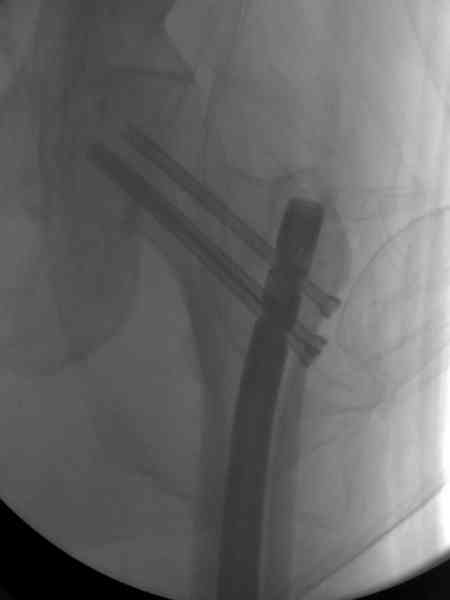

На второй день (7) обнаружен пропущенный перелом,

сделаны Компьютерная Томограмма

и проведены шурурпы через и спереди штифта без удаления.

Послеоперационные снимки